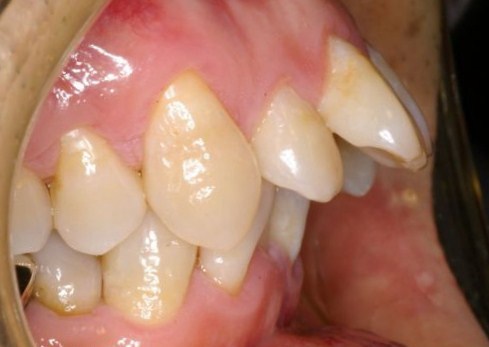

| @上顎前突(矯正用インプラント使用症例) | |||||||||||||||||||||||||||||||||||

かなり重度の上顎前突症例です。 バードフェイス(鳥貌)と言われる横顔で、以前(2000年頃まで)は矯正不可能と言われていた症例ですが 矯正用インプラント(矯正用ビス)を入れることにより、短期間で改善できた例です。 尚、矯正用インプラントは、力がかかる時だけ入れるもので使用後は簡単に外せます。 矯正用インプラントは、2000年頃より日本に導入された治療法です。(詳しくは、コチラ) もちろん、矯正用インプラントを使用しなくても治る症例も沢山あります。 |

上顎の歯槽骨までも後ろに後退させて側貌も改善されています。(顔は伏せています。) 歯並びだけではなく、顔の見た目も改善することが矯正の目標と考えています。 また、歯列もV字型の咬み合わせからU字型になって咬み合わせも良くなり、口元の審美性も改善されています。 |

| また、矯正期間をかなり短縮できる利点があります。 矯正期間1年6カ月 欠点は、インプラントを埋めることですが、小さなビス(長さ8mm直径1.8mm程度)なので簡単に出来ます。 また、インプラントを除去後は、粘膜、骨は完全に元に戻りますので心配いりません。 |